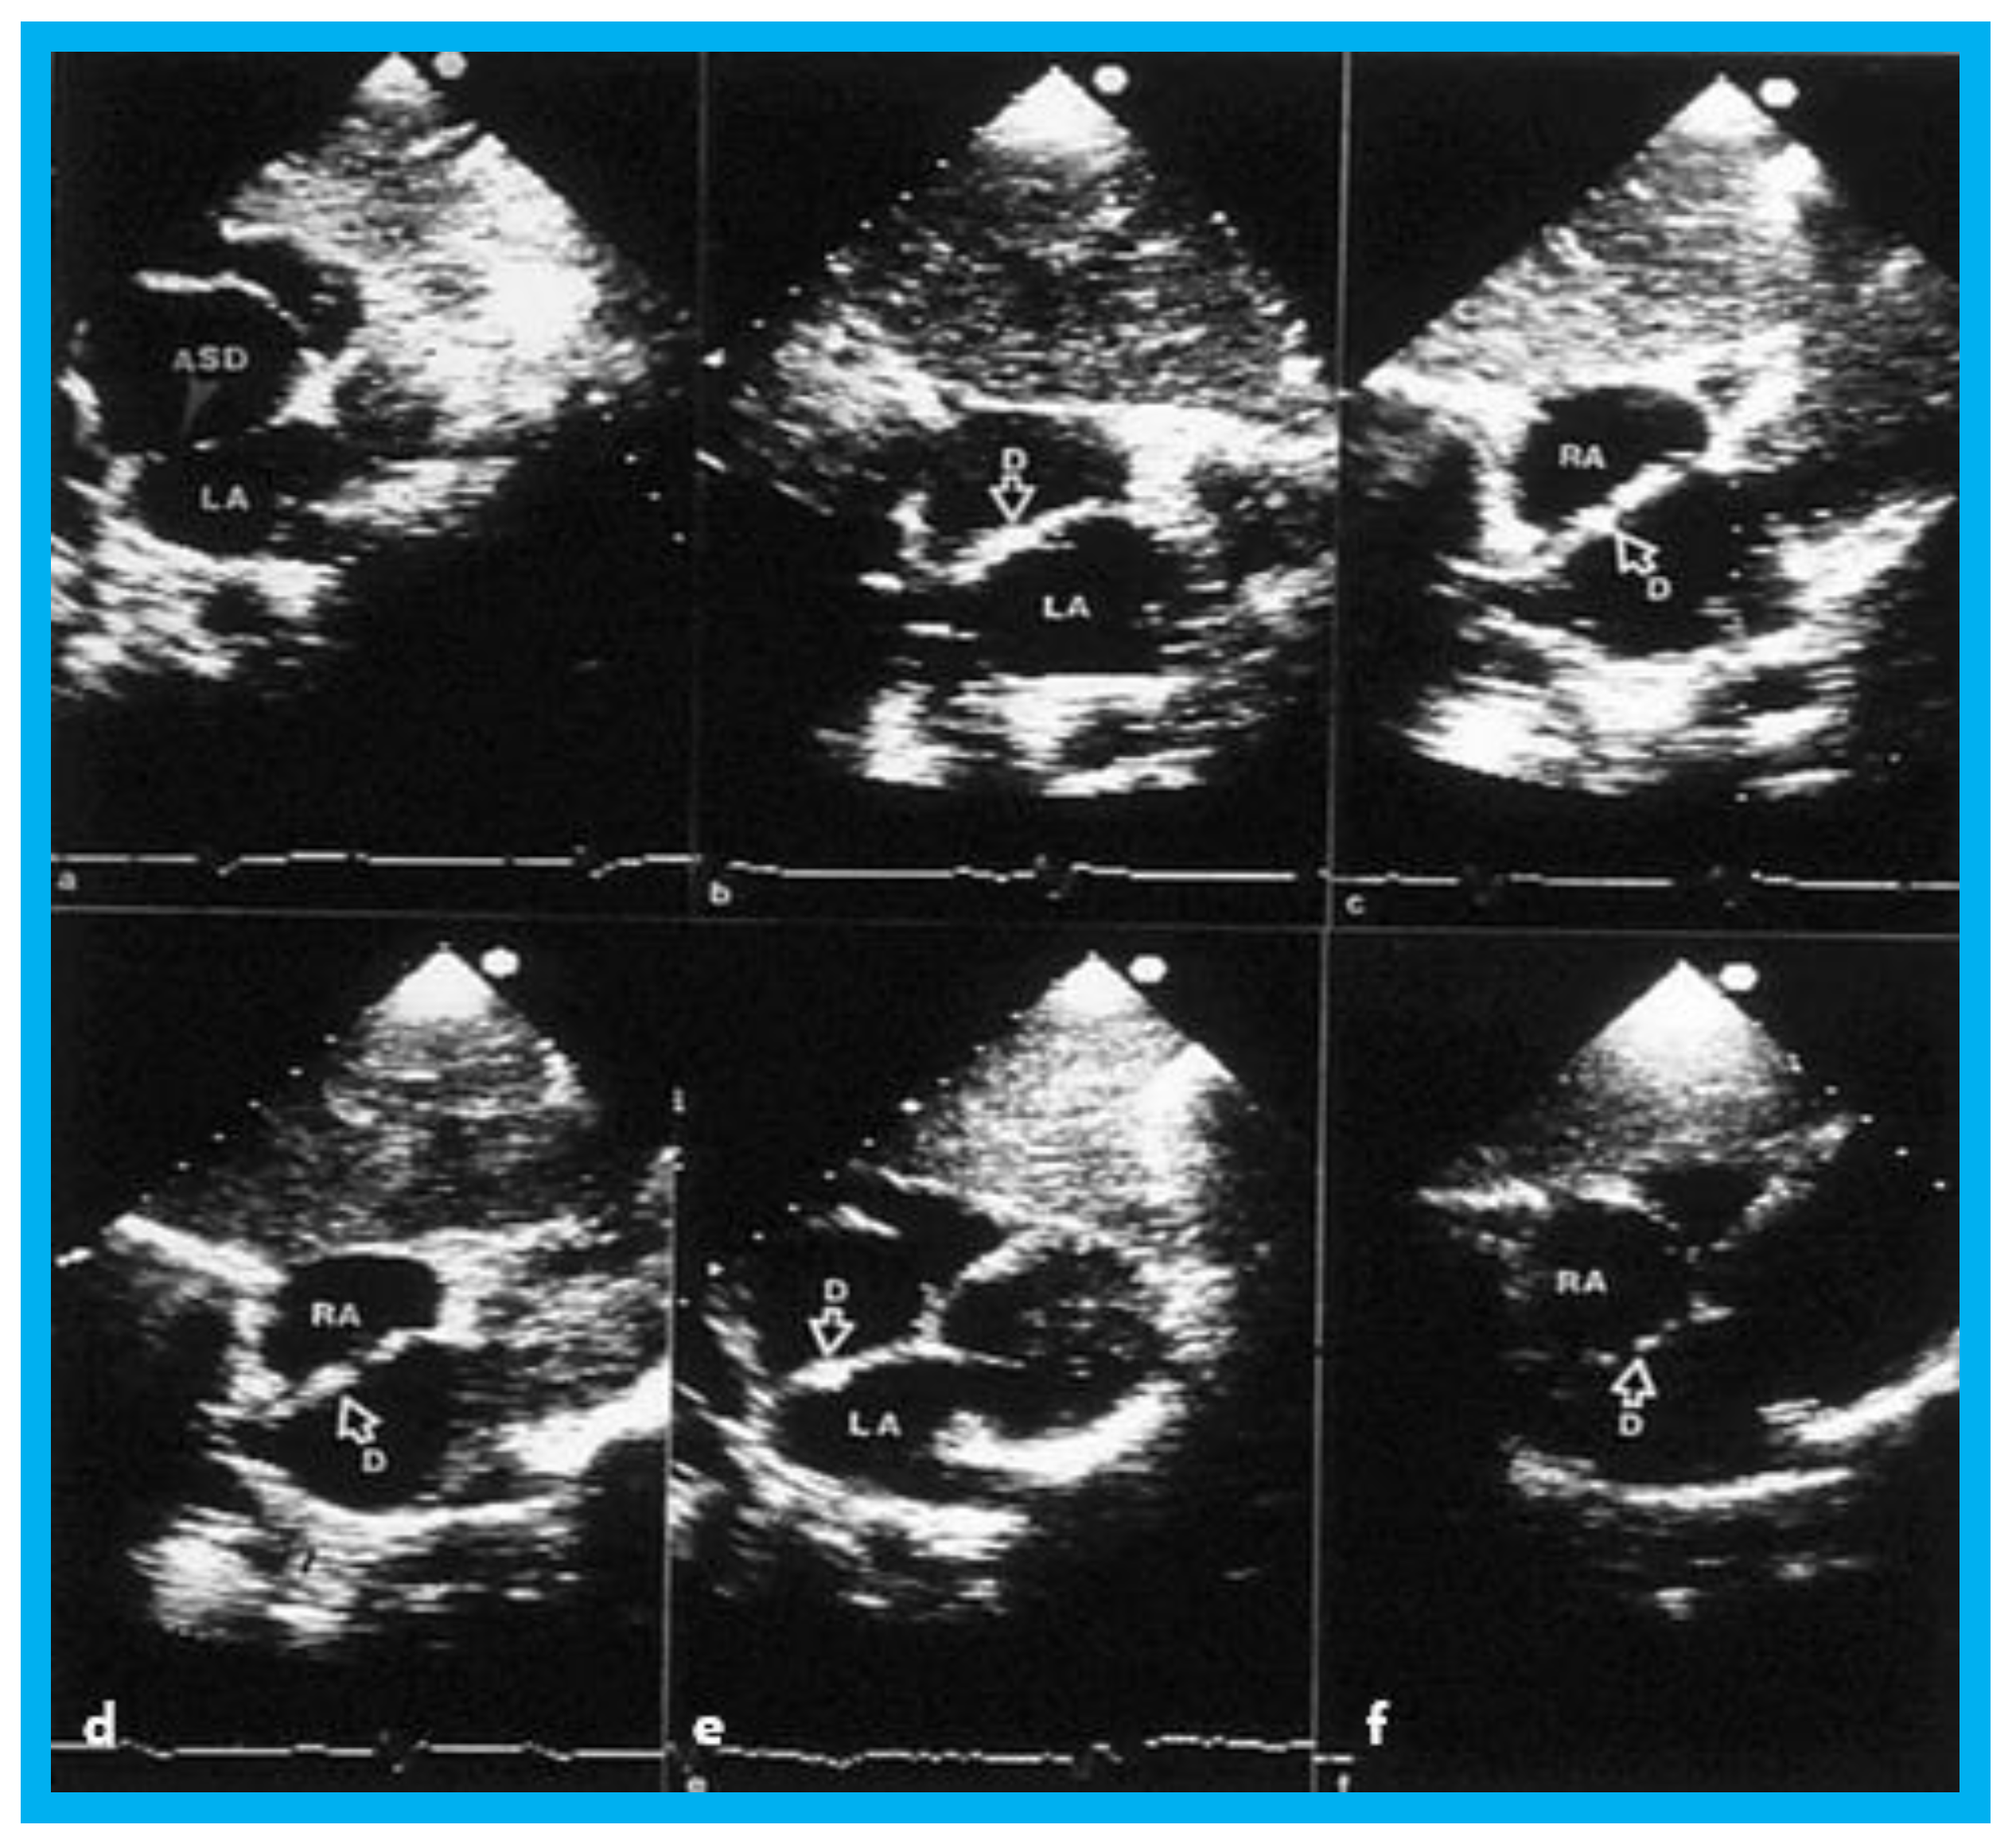

Transthoracic echocardiogram in case 1 showed dilated right atrium (RA) and right ventricle (RV) with a common pulmonary venous confluence (Figure 6a) and a vertical vein emptying into the innominate vein and superior vena cava (SVC) (Figure 6b,c). Dilated coronary sinus (CS) with mosaic color-Doppler flow pattern of pulmonary venous entry was also seen (Figure 6d,e). These findings indicated mixed type of total anomalous pulmonary venous connection. The findings in case 2 were very similar to those seen in case 1. However, not all pulmonary veins were identified and their course and connections to the pulmonary venous confluence could not be established. Therefore, catheterization and cineangiography were undertaken to validate the diagnosis prior to corrective cardiac surgery. Levo-angiographic frames following right pulmonary artery cineangiogram demonstrated entry of right pulmonary veins into the coronary sinus in both cases (Figure 7a,b,d). Direct injection into the left pulmonary vein via a catheter positioned into it via the innominate and vertical veins in the first case (Figure 7c) and on levo-angiogram following left pulmonary artery cineangiogram in the second case (Figure 7e) clearly demonstrated left pulmonary venous drainage via the vertical vein into the systemic venous circuit. Transesophageal echocardiography during surgery in both cases could not delineate the number of pulmonary veins and their connection with the confluence, although we had only access to single-plane TEE probe at that time.

Figure 6. Selected two-dimensional (a) and color flow images (be) of a patient (case 1) with mixed type of total anomalous pulmonary venous connection are shown. In (a), dilated right atrium (RA) and right ventricle (RV) and common pulmonary venous confluence (CC) are illustrated. In (b,c), spectral and color flow images demonstrate the vertical vein draining into the innominate vein and superior vena cava (SVC). In (d,e), dilated coronary sinus (CS) with mosaic color flow pattern of pulmonary venous entry are apparent. ARCH, aortic arch; LA, left atrium; LV, left ventricle. Reproduced from Reddy S.C.B., et al. [8].